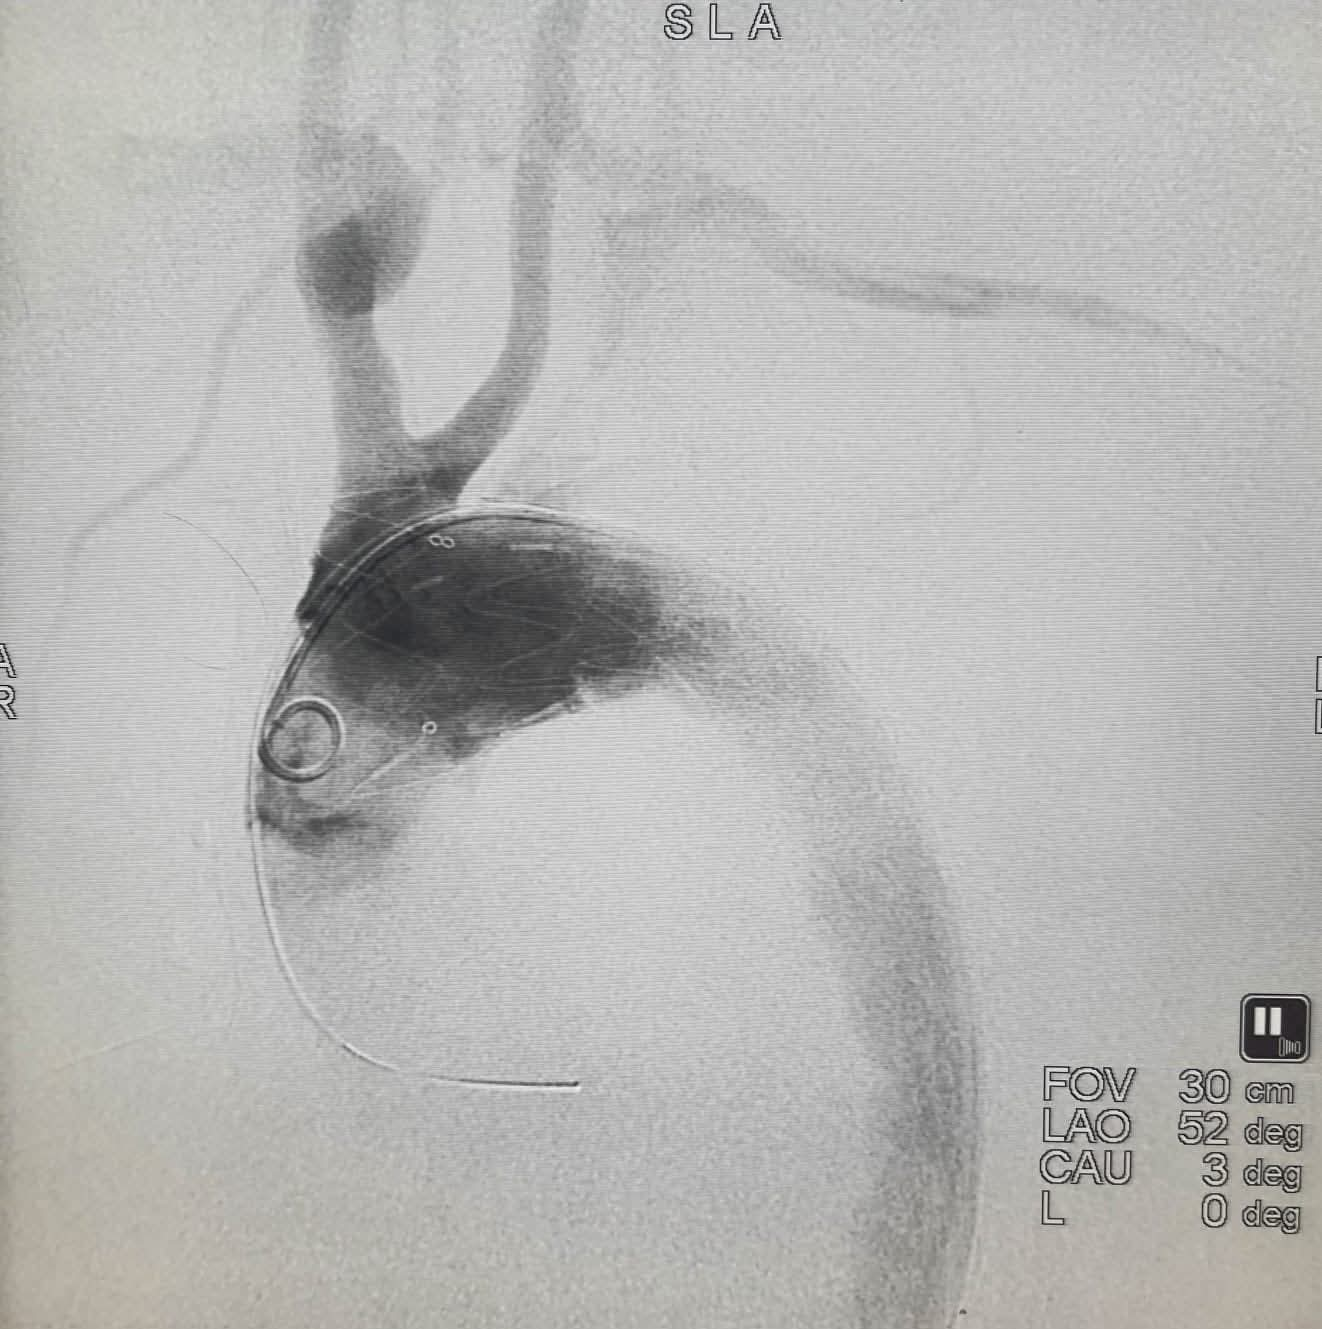

في إطار رؤية الأستاذ الدكتور/ محمد إسماعيل سليم، رئيس مجلس إدارة شركة الخدمات الطبية، بتطوير المنظومة العلاجية وتوطين أحدث الجراحات المتقدمة بمستشفيات الشركة، حقق فريق جراحة الأوعية الدموية بمستشفى ألماظة نجاحاً طبياً متميزاً بإنقاذ حياة مريض كان يعاني من انشطار وشرخ بالشريان الأورطي الصدري، وذلك عبر تقنية القسطرة التداخلية ودون اللجوء لفتح جراحي.

وقد تمت العملية بدقة عالية على مدار يومين بإشراف دكتورة/ غادة ماهر، النائب الطبي، ودكتور/ عبداللطيف الجيار، رئيس قطاع القاهرة؛ حيث قاد الأستاذ الدكتور/ عاطف عبد الحميد الفريق الطبي لإجراء جراحة توصيل الشريان السباتي بالرقبة أولاً، ثم تركيب الدعامات المغطاة لغلق التمدد الشرياني في اليوم التالي، بمعاونة متميزة من أطقم التخدير والرعاية المركزة والتمريض.